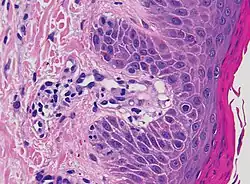

| Lichen planus | Irregular epidermal hyperplasia with a jagged “sawtooth” appearance, compact hyperkeratosis or orthokeratosis, foci of wedge-shaped hypergranulosis, basilar vacuolar degeneration, slight spongiosis in the spinous layer, and squamatization. The dermal papillae between the elongated rete ridges are frequently dome shaped. Necrotic keratinocytes can be observed in the basal layer of the epidermis and at the dermal-epidermal junction. Eosinophilic remnants of anucleate apoptotic basal cells may also be found in the dermis and are referred to as “colloid or civatte bodies”. Whickham striae are usually seen in the areas of hypergranulosis. Vacuolar degeneration at the basal layer may be noted leading to focal subepidermal clefts (Max Joseph spaces). Squamatization occurs as a result of maturation and flattening of cells in the basal layer. It happens in areas of marked hypergranulosis with prominence of the sawtooth pattern of rete ridges. Wedge-shaped hypergranulosis can occur in the eccrine ducts (acrosyringia) or hair follicles (acrotrichia). In the hypertrophic subtype, the associated hyperkeratosis, parakeratosis, hypergranulosis, papillomatosis, acanthosis, and hyperplasia markedly increased with thicker collagen bundles forming in the dermis. Moreover, the rete ridges are more elongated and rounded as opposed to the typical sawtooth pattern. In atrophic LP, loss of the rete ridges and dermal fibrosis is prominent. In vesiculobullous LP, the disease progression is quicker. Hence, some of the distinctive features such as hyperkeratosis, hypergranulosis, or dense lymphocytic dermal-epidermal infiltrate may not be present. LP lesion may resolve with residual hyperpigmentation caused by a persistent increase in the number of melanophages in the papillary dermis.[9] | ![]() |

|

| Lichenoid drug reaction |

Can virtually be indistinguishable from cutaneous LP both clinically and histopathologically.